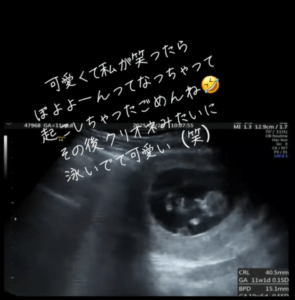

ママさんが『ぽよよーん』と表現したその一連の動きは、多くの人の注目を集めることに。投稿には「母性が溢れ出す…!」「クリオネちゃん」「可愛すぎる」などの声が寄せられていました。

エコーを通して初めて見た赤ちゃんの姿に「心臓もしっかり動いていて、懸命に生きている姿に感動しました」と当時を振り返るママさん。

泳いでいる様子(@kokogun5656さんより提供)